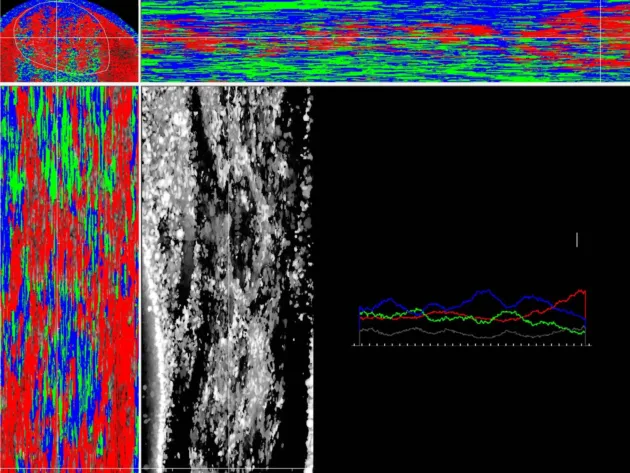

Enhance Your UTC Experience. Need accessories for your UTC Imaging system? You’ve come to the right spot!

Interested in acquiring the full UTC system? Let us craft a customized quote just for you. Click here for a personalized consultation—we’ll reach out to you shortly.